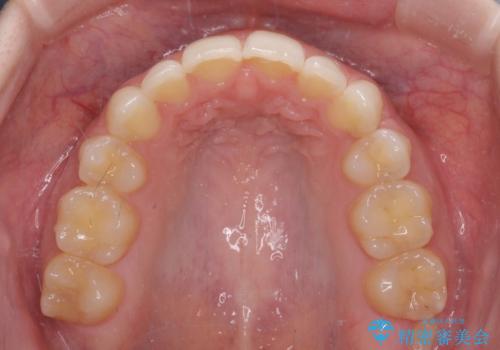

下顎の骨格的なズレが大きかったため、上下歯列のバランスが取れるか心配でしたが、上下ともに左右対称に近い歯列で治療を終えることができました。